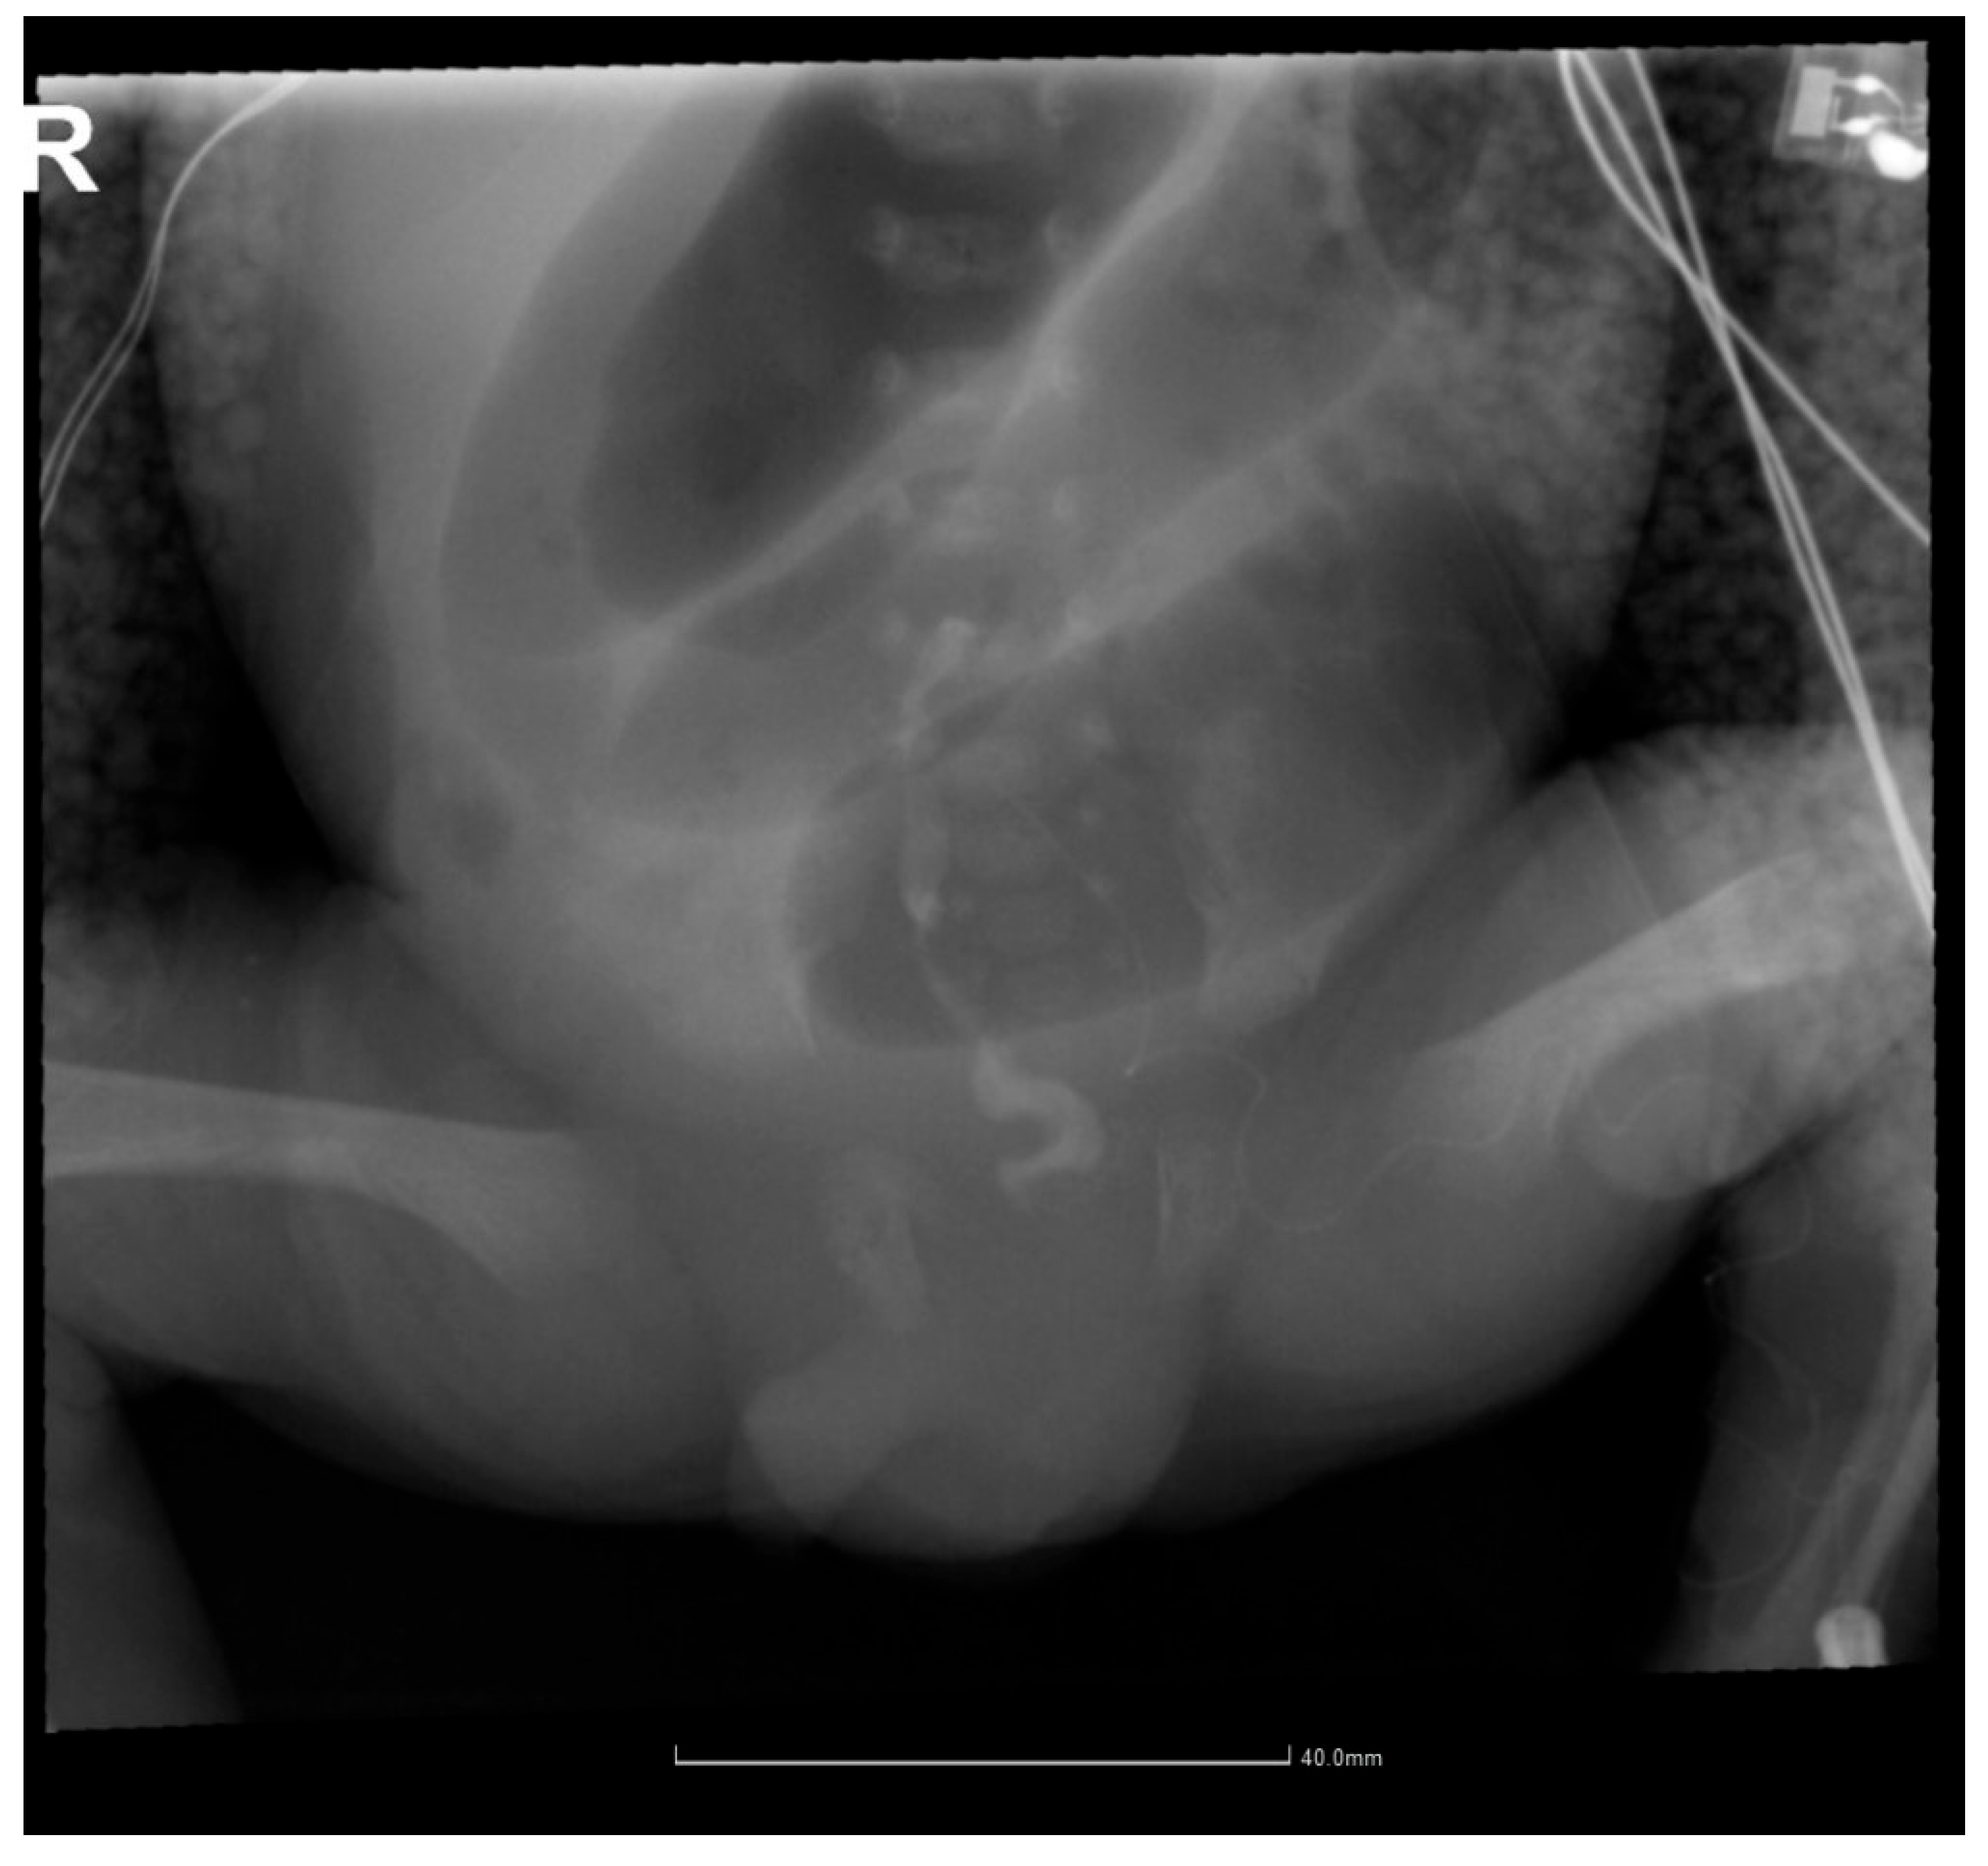

2.4. Gastrointestinal Complications and Diagnosis

2.5. Postoperative Course and Complications

| Day 12 | Intestinal obstruction suspected | Surgical consultation |